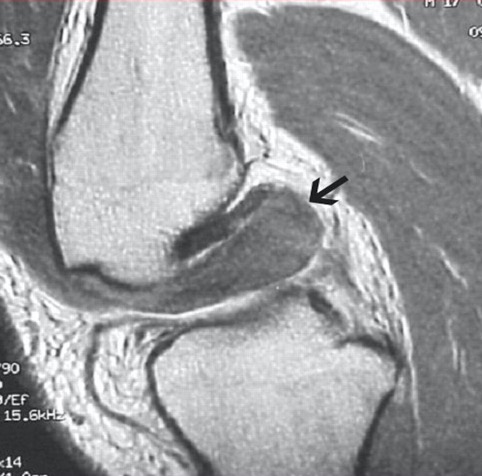

Medial dimpling Entrapped vastus medialis post knee dislocation on Coronal and Sagittal MRI

Sagittal MRI demonstrating patella tendon avulsion and ACL / PCL tear

Sagittal MRI demonstrating complete tear of ACL and PCL

Sagittal MRI demonstrating complete tear of ACL and mid substance tear of PCL